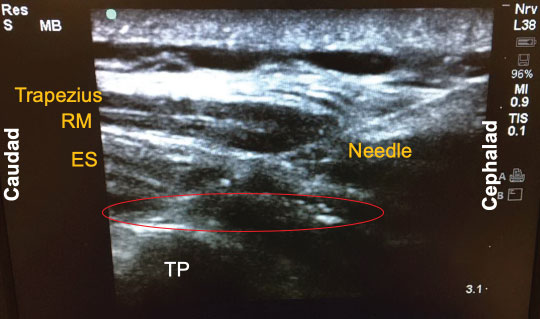

Since its introduction a few years ago, there have been numerous descriptions published on how to perform the ESP block. The following is a brief summary of the technique used to perform the block on our previously-described patient. With the patient in the sitting position, a high-frequency linear ultrasound probe was placed longitudinally on the patient's back approximately 3 cm lateral to the 5th thoracic (T5) spinous process. Three muscles above the hyperechoic transverse process were identified: trapezius, rhomboid major, and erector spinae in order of superficial to deep layers (Figure 1). A 10-cm 18-gauge Tuohy needle was inserted in-plane with the ultrasound beam at a 30° angle in a cephalad to caudal fashion. The tip of the needle was directed to the myofascial plane between the erector spinae muscle and the T5 transverse process (Figure 2). Following negative aspiration of blood, 20 mL of 0.25% ropivacaine was incrementally injected. Linear fluid spread deep to the erector spinae muscle was visualized in real-time. Finally, for continuous postoperative infusion, a 20-gauge catheter was threaded through the Tuohy needle and secured at the skin with a goal of having 5 cm of catheter left in the myofascial plane.

Figure 2: Local injection into the erector spinae (ES) plane. The tip of the needle (red circle) was directed to the myofascial plane between the erector spinae muscle and the T5 transverse process (TP). RM: Rhomboid Major.